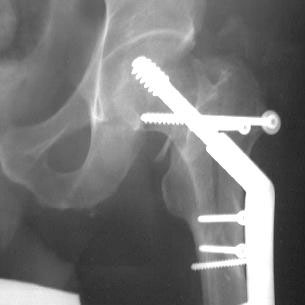

We decided to fix the Lt femur with a few lag screws on the proximal part andstabilize the femur with long Richard plate that was inserted in a sub-muscularfashion, in order to avoid opening the main shaft fx (the so-called biologicfixation - see Lt leg incisions.).

On the Rt side I replaced the recon nail with a longer one (accepting its toolateral and anterior entering point), I added a proximal locking screw (anterior toposterior) in the subtrochanteric region through a self-made extra hole, and two 6.5cancellous hip screws posterior to the nail.

Lt femur

Lt hip

Lt leg incisions